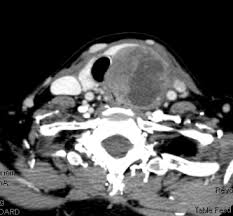

Cancer Volume Doubling Time In The Active Surveillance Of Papillary Thyroid Carcinomas

Cancer Volume Doubling Time In The Active Surveillance Of Papillary Thyroid Carcinomas from www.thyroid.org